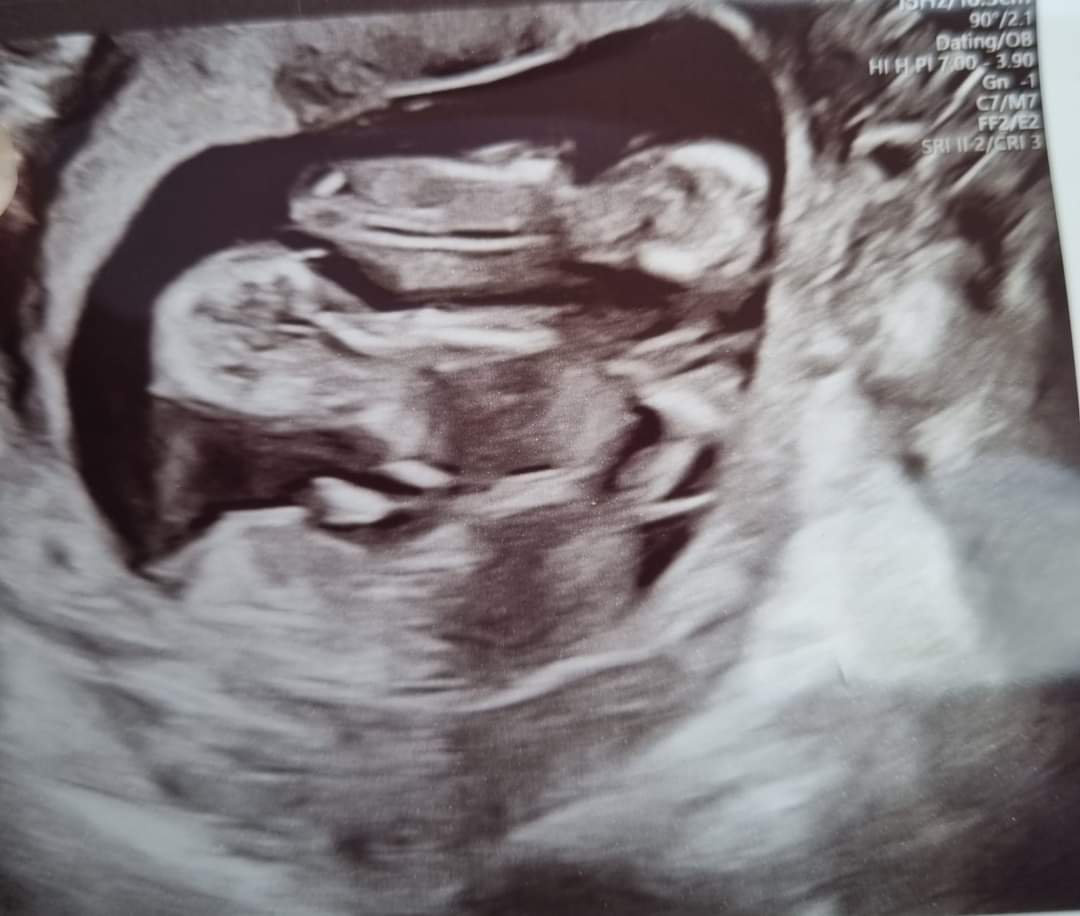

James Casper, 26 ans, et Jenni Casper, 27 ans, de Selby, vivent à Yorks dans le nord de l’Angleterre Ils ont été informé dans un premier temps qu’ils attendaient des jumeaux, cependant ils sont restés sans bouche bée en apprenant, lors de l’examen de Jenni à la 12e semaine, qu’ils attendaient en fait des triplés.

Lors de l’examen de 20 semaines, ils ont découvert que les triplés étaient identiques.

Jenni a ensuite envoyé à son mari des photos du scanner avec leurs trois petites têtes réunis et il en est resté bouche bée.